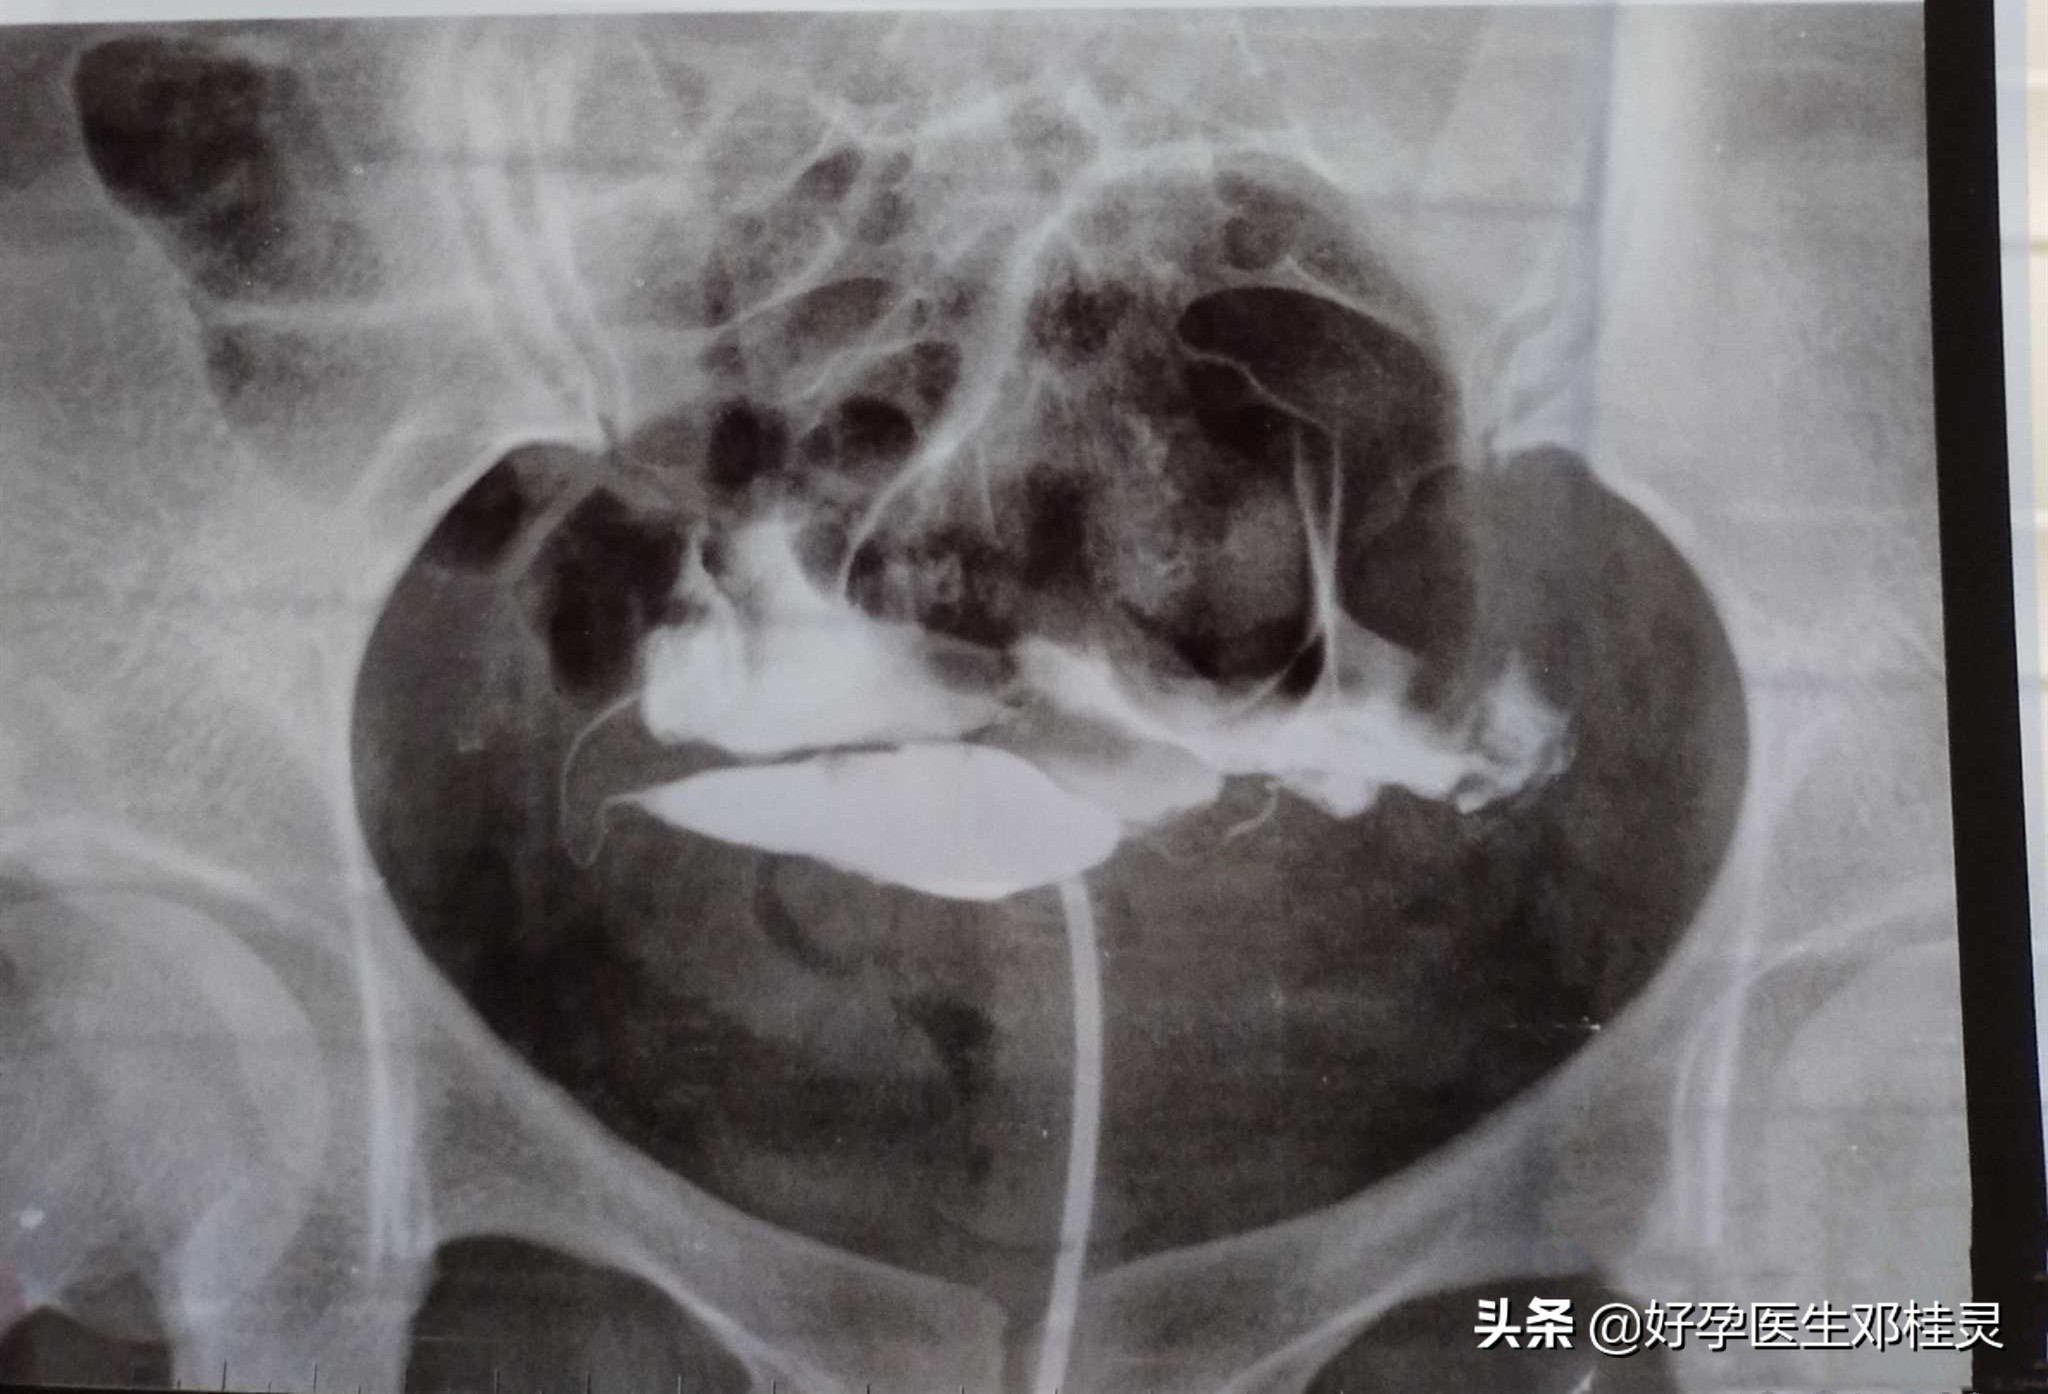

德州王女士今年36岁,三胎十年没怀孕,一开始年龄小也没有检查过,直到近两年开始出现腹部两侧疼痛,而且想要个三胎,经过一番周折才找到我。经过检查后发现她是双侧输卵管梗阻、粘连,我当时看了她的输卵管造影之后,都非常惊讶:“输卵管都粘成一团了,咋没早点检查啊?”

3、再次,引发其他炎症,盆腔炎、子宫内膜炎等。输卵管很容易与盆腔粘连,像王女士这种就是,不只是输卵管梗阻、粘连,输卵管外部与盆腔也粘连在一起,基本快找不出输卵管的位置了。粘连发炎导致慢性盆腔炎症是临床上很多女性患者的真实情况,由于输卵管与子宫连接,输卵管炎症会逐渐蔓延到子宫,导致子宫内膜炎症、异位症等,为不孕再加上一把“大锁”。